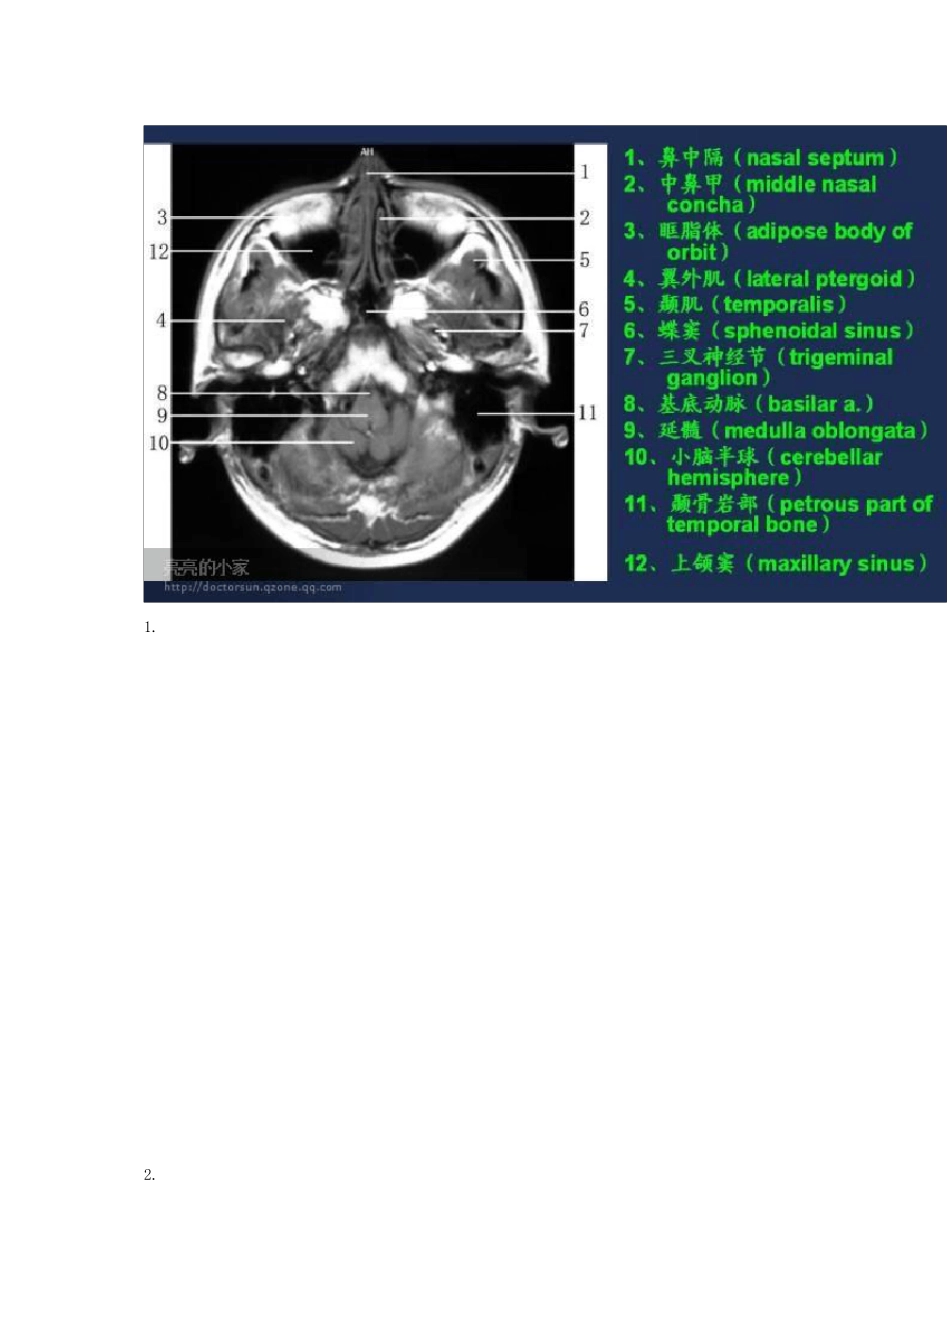

头颅MRI(磁共振成像)断层图谱